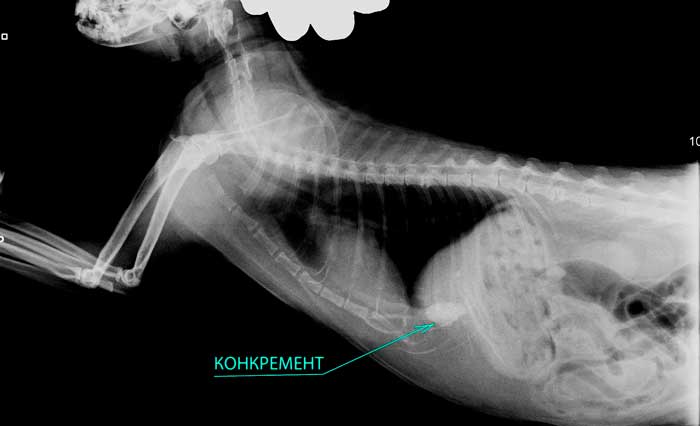

Рентгенологическая диагностика саркомы у кошек

Раздел: Визуальный дайджест